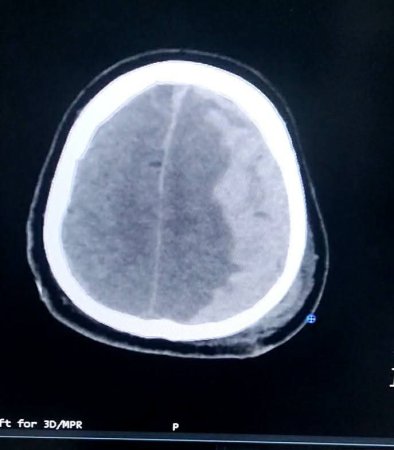

Під час детального огляду лікарі діагностували вкрай небезпечний клінічний стан — тріаду Кушинга:

Брадикардія (критичне сповільнення серцебиття);

Високий артеріальний тиск;

Патологічне дихання.

Це поєднання симптомів свідчить про те, що внутрішньочерепний тиск сягнув критичної позначки, фактично «тиснучи» на мозок зсередини.

Щоб знизити цей тиск і не допустити незворотних змін у мозку, бригада застосувала метод короткочасної гіпервентиляції під суворим контролем капнографії (моніторингу рівня вуглекислого газу).